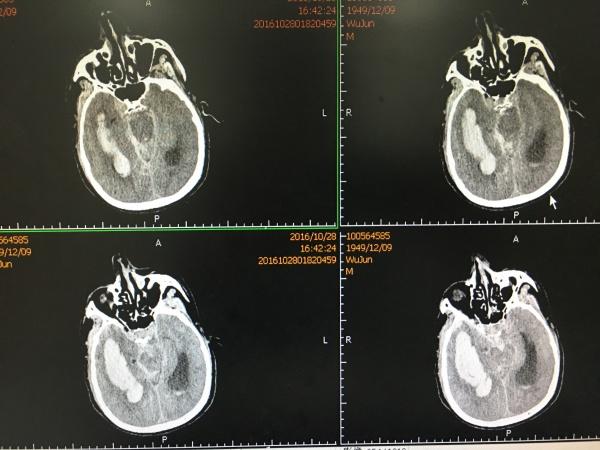

我们急诊在全麻下行开颅血肿清除+动脉瘤夹闭+颅内压监护探头植入术,术后复查头颅CT如下:

手术顺利,效果满意,术后第4天再次复查头颅CT:

见MCA供血区大面积梗塞,查凝血无明显异常,予以改善微循环、扩容等对症治疗,1周后再次复查CT: